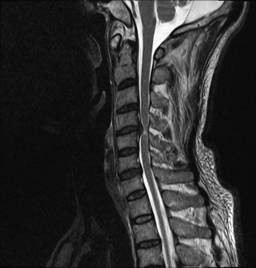

中年男性41歲,因“行走不便2年,加重伴雙手麻木2周”之主訴入院,癥狀主要為:頸部疼痛、僵硬,雙下肢無力、行走不穩(wěn),雙手麻木,協(xié)調性差,右手握筆困難。入院查體:步態(tài)不穩(wěn),C3-C7壓痛、叩擊痛,肢痛溫覺減退,雙上肢肢肌力5-級,雙下肢肌力4-級,肌張力增高,雙下肢腱反射亢進,病理征(+),行頸前路小切口突出椎間盤切除、前路頸椎橋形鎖定植骨融合(ROI-C假體),無需前路鋼板,術后四肢麻木明顯緩解,右上肢精細動作明確增強,可寫字,行走不穩(wěn)消失,肌力基本正常,頸部活動度無明顯受限。(圖1、圖2)

圖1:術前頸椎MRI提示頸椎退行性變,C4/5椎間盤突出、脊髓出現(xiàn)高信號改變,C4硬膜囊受壓變形。